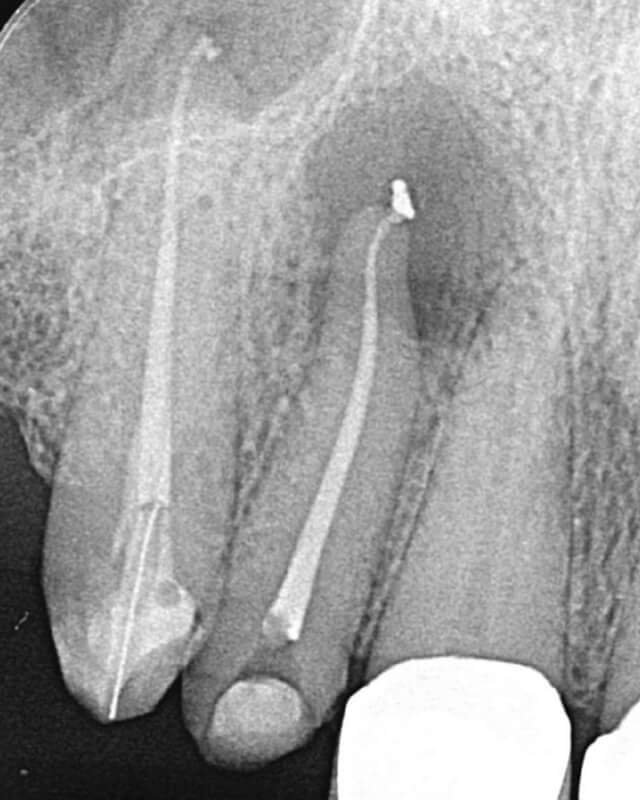

Endodonția este o ramură esențială a stomatologiei, axată pe diagnosticarea, prevenirea și tratamentul afecțiunilor pulpei dentare și a țesuturilor periapicale. Această specialitate joacă un rol crucial în salvarea dinților naturali, evitând extracțiile și menținând sănătatea orală pe termen lung. Prin tehnici avansate și echipamente de ultimă generație, endodonția asigură tratamente precise și eficiente, contribuind la redarea sănătății și funcționalității dinților într-un mod durabil și predictibil.

Utilizarea tehnicilor moderne asigură un tratament rapid, precis și confortabil pentru pacient.

Tratamentele corecte reduc riscul de infecții și complicații viitoare.